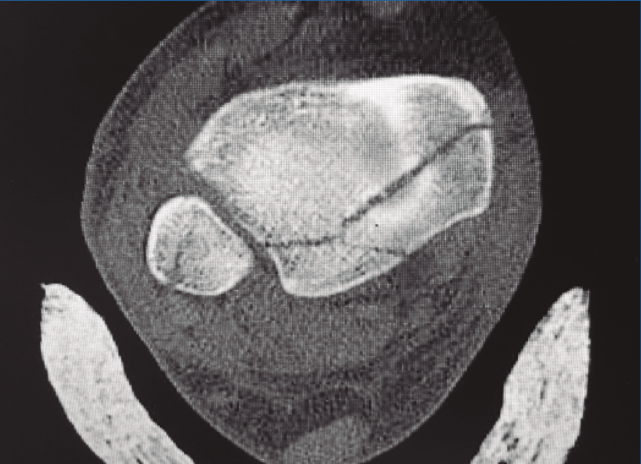

La clasificación de Bartoníček y Rammelt(14)(Tabla 2), publicada en 2015, está basada en 141 casos consecutivos de fracturas de tipo Weber B o C con fractura de MP analizadas por TC en planos transverso, horizontal y frontal, y reconstrucción 3D. Las fracturas fueron clasificadas en 5 tipos, con especial referencia a la afectación de la incisura fibular de la tibia: el tipo 1, fragmento extraincisural, es una fractura extraarticular; el tipo 2, fragmento posterolateral, es la más frecuente; el 3, fragmento posteromedial en 2 partes (Figura 2); el 4, gran fragmento triangular posterolateral, donde puede apreciarse el signo de doble contorno; y el tipo 5, una fractura irregular osteoporótica, que no puede encuadrarse en ninguno de los tipos anteriores.

Figura 2. Imagen de tomografía computarizada de una fractura de tipo 3 de Bartoníček y de tipo II de Haraguchi.